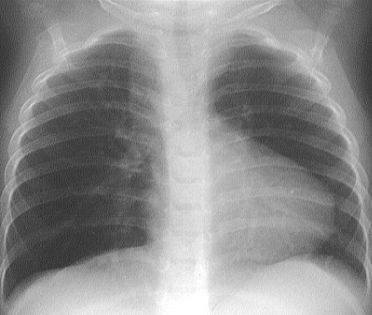

Tứ chứng Fallot trên x quang

Chụp X-quang ngực có thể cho thấy cấu trúc của tim và phổi. Một trong những triệu chứng điển hình của tứ chứng Fallot trên X-quang là tim hình chiếc giày (Boot-shaped Heart) do tâm thất phải bị phì đại. Cùng eLip tìm hiểu những thông tin ngay dưới đây để hiểu rõ hơn nhé!

Tứ chứng Fallot, là một trong những rối loạn tim bẩm sinh phổ biến nhất, bao gồm tắc nghẽn đường ra thất phải, khiếm khuyết vách liên thất, động mạch chủ cỡi ngựa, và phì đại thất phải. Tỷ lệ tử vong ở những bệnh nhân không được điều trị là 50% vào năm 6 tuổi, nhưng trong thời đại hiện nay phẫu thuật tim trẻ em với các hình thức đơn giản, tứ chứng Fallot tồn tại lâu dài với chất lượng tuyệt vời của cuộc sống.